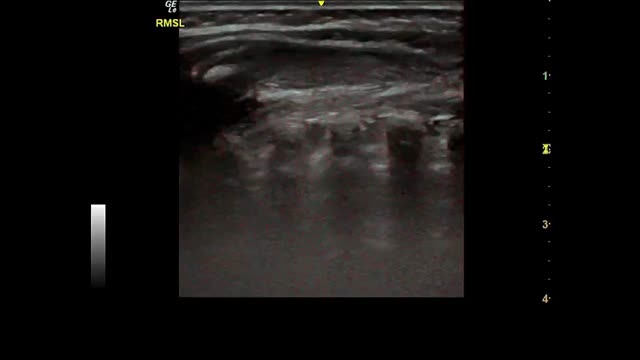

Most of the studies under analysis had LU findings in common in the presence of SARS-CoV-2 infection. The most common finding was B lines, which had very distinct characteristics, 34 of which reported focal, diffuse and confluent B lines.12,15,18,19,25,26,27,29,30,31,32–35,38,62,67,68,70,72–74,77–88 Twenty-nine studies described consolidations of different types: small, large, linear, subpleural, multifocal and translobar,12,15,18,19,25,26,27,29,30,33,35,38,62,63,67,68,70,72,73,75,78–80,82–85,87,89 associated with white lung12,30 and with air bronchograms18,38. Nineteen studies described pleural irregularities,12,15,18,26,27,30,32,33,35,62,70,72,77,79,80,82,84,85,89 and 19 reported pleural and subpleural line alterations, such as thickening or shred sign.18,19,26,29,31,32,34,38,62,67,70,72,73,75,77,80,85 Ten studies referred to pleural effusion,38,62,67,70,72,75,77,82–84 8 reported bilateral findings15,34,63,79,82,86,87,88 and 3 revealed preponderance of compromise in posterior areas.79,80,89 Three studies associated appearance of A lines during recovery 35,67,80 and most of the papers reported the LU role in the serial evaluation of patients with COVID-19.27,29,30,33,35,67,68,70,71,72,74,75–77,80

Some studies reported radiological findings agreement between LU and HCRT.15,18,25,27,29,32,33,35,38,62,63,65,68,70,78,79,83,84,87,89 The main HCRT findings were ground glass opacities, “crazy-paving” pattern, consolidations, pulmonary infiltrates and pleural thickening as well as interlobular septal thickening.18,29,32,33,35,38,62,65,68,70,73,75,78,79,81,83–85,87,89 When comparing thorax HRCT features with those of LU in pneumonia resulting from COVID-19 the findings included (i) correlation of ground glass opacity with B lines (multifocal, discrete or confluent); (ii) presence of thickened pleura in HRCT with thickening of the pleural line in LU; (iii) pulmonary infiltrates as confluent B lines in LU; (iv) pulmonary consolidation in both techniques20 The finding “white lung” was also described as ground glass opacity in HRCT.15,18,26,27,38,62,78,87

Fig. 2 shows the main findings of the LU imaging described in the study.